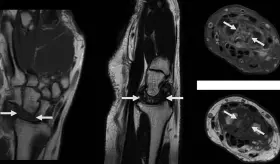

Tras múltiples evaluaciones cardíacas normales, estudios de imagen revelaron un schwannoma espinal a nivel D6-D7 como causa del dolor torácico neuropático.

La paciente fue diagnosticada con endometriosis del nervio ciático derecho tras años de dolor incapacitante y diagnósticos erróneos.